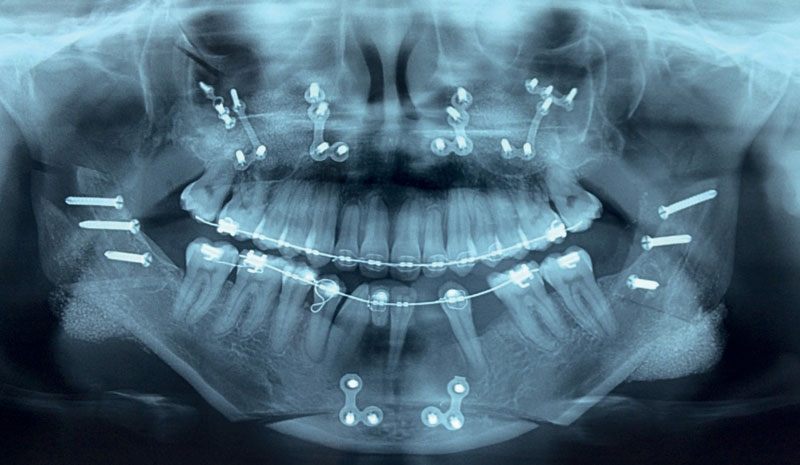

Figure 3a.

Figure 3b.

Figure 3c.

Figure 3: A patient undergoing a facial makeover procedure. a) Long-face with bilateral non-slender hemimandibular elongation. b) One year after two surgeries: a transpalatal distraction for smile aesthetics; upper jaw impaction, lower jaw set-back, bilateral malar valgisation, impaction and advancement genioplasty, tip rhinoplasty and jaw angle projection. c) Orthopantomogram showing both lateral and vertical augmentation of the jaw angle with HA/fibrin glue onlay. The caudal augmentation with this technique is less reliable, but it obviated a third surgery with 3D print augmentation.